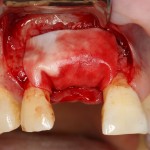

В этом случае остеопластика делается отдельной процедурой. Ее принципы точно те же, но уже без импланта. Например:

Имплантировать в таких условиях — заведомо обрекать себя на хреновый, с точки зрения эстетики и функциональности, результат. Поэтому первым этапом проводим остеопластику. Объем небольшой, использовать в таких объемах костный блок не очень рационально. Воспользуемся аутокостной стружкой и мембраной.

Сначала фиксируется BioGide. Это легко:

Затем укладывается и конфигурируется аутокостная стружка:

Если после этого BioGide намочить физраствором, им легко укрыть получившийся объем: